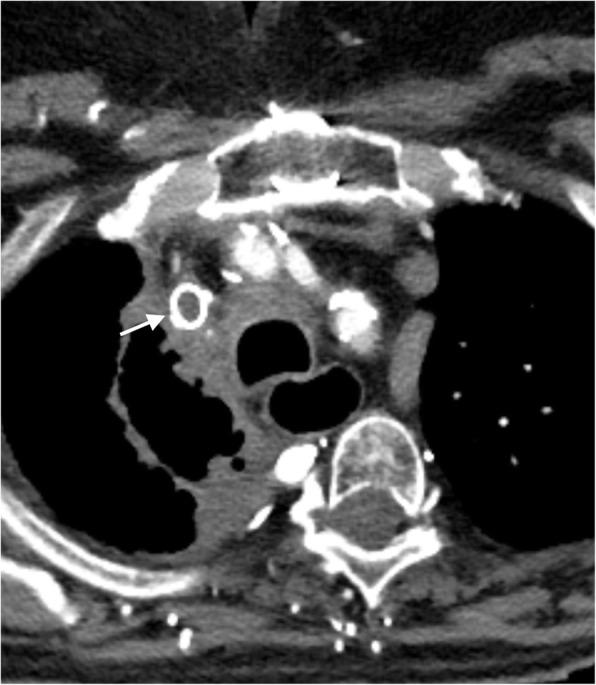

In the healthy patient, blood returns to the heart via classic venous pathways. Obstruction of any one of these pathways will result in blood flow finding new collateral pathways to return to the heart. Although significant anatomic variation exists and multiple collateral vessels are often present in the same patient, it is a general rule that the collateral pathways formed are a function of the site of venous blockage. Therefore, knowledge of typical collateral vessel systems can provide insight in localizing venous obstruction and characterizing its severity and chronicity. In addition, knowledge of collateral anatomy can be essential in interventional procedural and/or surgical planning, especially when placing catheters in patients with venous blockage. In this pictorial review, we provide a systematic approach to understanding collateral pathways in patients with venous obstruction in the upper body.

在健康患者中,血液通过经典静脉途径回流至心脏。这些途径中任何一条受阻都会导致血流寻找新的侧支途径回流至心脏。尽管存在显著的解剖变异,且同一患者体内常存在多条侧支血管,但一般规律是,形成的侧支途径取决于静脉阻塞的部位。因此,了解典型的侧支血管系统有助于定位静脉阻塞并判断其严重程度和慢性化情况。此外,了解侧支解剖结构对于介入操作和/或手术规划至关重要,尤其是在为静脉阻塞患者放置导管时。在本图文综述中,我们提供了一种系统方法,用于理解上身静脉阻塞患者的侧支途径。